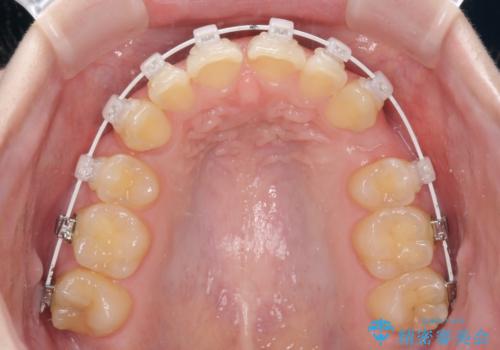

- 矯正装置

- 審美装置

- 1年6ヶ月

- 10-30回